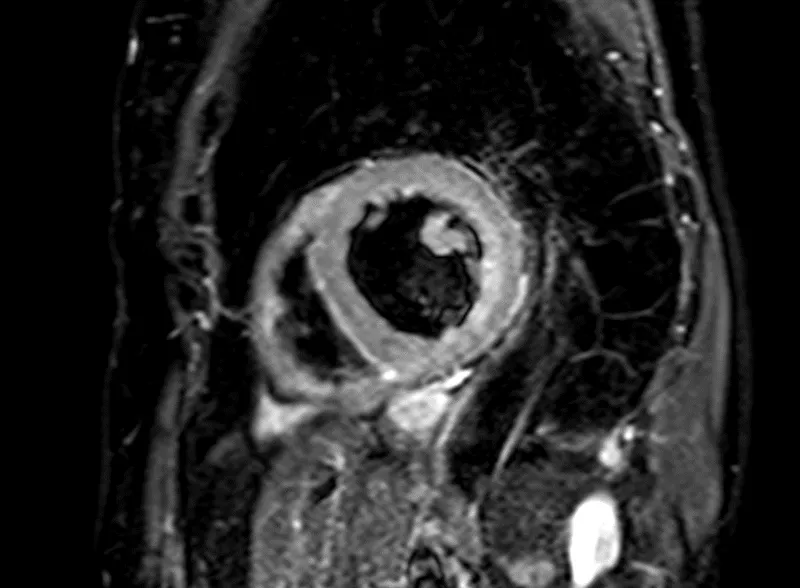

Vyšetření MRI srdce je bez známek edému myokardu a pozdního gadoliniového sycení (LGE) – nezjistilo tedy přítomnost zánětu, nekrózy, nahrazující fibrózy či infiltrace myokardu. Levá komora hodnocena při MRI jako mírně dilatovaná s EF 39 % (obrázek 2, video 4). Laboratorní vyšetření CK, LDH a železa, provedené k vyloučení dalších možných etiologií DKMP, bylo bez významné patologie, hodnota NT-pro BNP poklesla na 1 120 ng/ml.

Obr. 2. MRI srdce. 2A – nepřítomnost edému myokardu v T2 STIR TSE sekvenci v krátké ose, 2B – IR TFE sekvence v krátké ose – bez detekce pozdního sycení myokardu (LGE)

Video 4. MRI srdce, B-TFE sekvence v dlouhé ose – mírná dilatace a difúzní hypokineze stěn LK s EF 39 %

Na základě provedených vyšetření se domníváme, že etiologií srdečního selhání je u nemocné nejspíše dilatační kardiomyopatie na podkladě kardiotoxického postižení myokardu protinádorovou léčbou antracykliny – pozdní kardiotoxicita. Vzhledem ke zlepšující se systolické funkci LK s EF 39 % dle MRI jsme ustoupily od přístrojové léčby – implantace ICD.